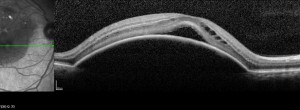

Optical Coherence Tomography Assessment of Apparent Foveal Swelling in Patients with Foveal Sparing Secondary to Geographic Atrophy.

GAIN. Characterization of geographic atrophy progression in patients with age-related macular degeneration: evolution and risk factors associated with geographic atrophy progression